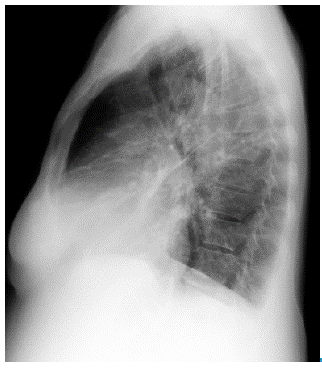

Initial studies included total blood count (normal), electrolytes (sodium:137 mEq/Lt, potassium: 3.82 mEq/Lt, chlorine:103 mEq/ Lt), urine test (normal), arterial blood gases interpreted at 560mmHg atmospheric pressure, which showed a chronic compensated respiratory acidosis without oxygenation disorder (pH 7.38; partial pressure of carbon dioxide (pCO2): 38.9mmHg; bicarbonate (HCO3): 23.6 mE-q/L; base excess: -1.7; oxygen partial pressure (pO2): 95.1mmHg; ratio PaO2/FiO2: 297, lactate 0.8 mmol/L), creatinine and blood ureic nitrogen (1.1 mg/dl and 29.25 mg/dl, respectively). Chest radiography showed an increased cardiothoracic index and signs of pre-capillary pulmonary hypertension (Figure 2a and 2b).

Left lateral view of chest radiograph. Both projections show pneumonia in the anterobasal segment of the left lower lobe and inferior lingular segment, right middle lobe atelectasis, enlarged cardiac size with pleural effusion and pericardial effusion. Additionally, signs of precapillary pulmonary hypertension can be observed.

Fig 2B: Left lateral view of chest radiograph. Both projections show pneumonia in the anterobasal segment of the left lower lobe and inferior lingular segment, right middle lobe atelectasis, enlarged cardiac size with pleural effusion and pericardial effusion. Additionally, signs of precapillary pulmonary hypertension can be observed.

Source: Own elaboration based on the data obtained in the study.